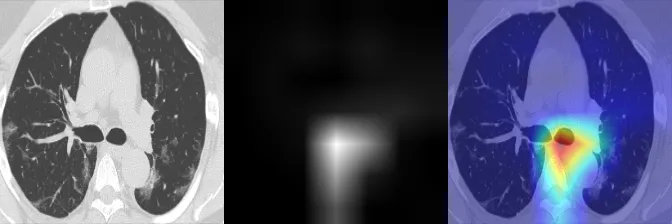

GradCAM visualization

EigenCAM visualization

HiResCAM visualization